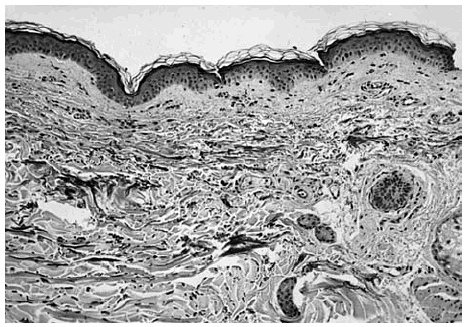

Las tinciones específicas (tricrómico de Masson, tinción para fibras elásticas) revelaron una disminución/ desaparición de las fibras elásticas en la dermis papilar y reticular superficial en ambos casos (fig. 4).

Fig. 4.--Piel afecta (caso 1): desaparición de las fibras elásticas en la dermis papilar y reticular (tinción fibras elásticas ×100).